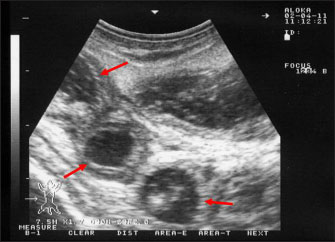

Ultrasonography has been proven effective for the early detection of several abdominal and thoracic disorders in small ruminants (Tharwat et al., 2012b; Tharwat and Al-Sobayil, 2017; Tharwat, 2021; Sadan et al., 2023; Tharwat and Al-Hawas, 2024a,b; Tharwat et al., 2024; Tharwat et al., 2025b). Recently, the technique has been found valuable for the diagnosis of various bacterial and parasitic infections in ruminants (Tharwat and Tsuka, 2024). An overall increase in intestinal mucosa thickness was detected in goats with PTB. It was classified as either mild, moderate, or severe (Fig. 2). Corrugation and folding of the intestinal mucosa may be also imaged in goats with PTB (Fig. 3). However, remarkable enlargement of the mesenteric lymph nodes are the most important findings in goats with PTB (Fig. 4). Other sonographic changes included increased hepatic brightness, intestinal edema consolidated lungs, and pleural, peritoneal, and pericardial effusions (Tharwat et al., 2012b).

Fig. 3. Ultrasonography of the corrugated intestinal mucosa in a goat with paratuberculosis. The lesion (red arrows) was best imaged longitudinally